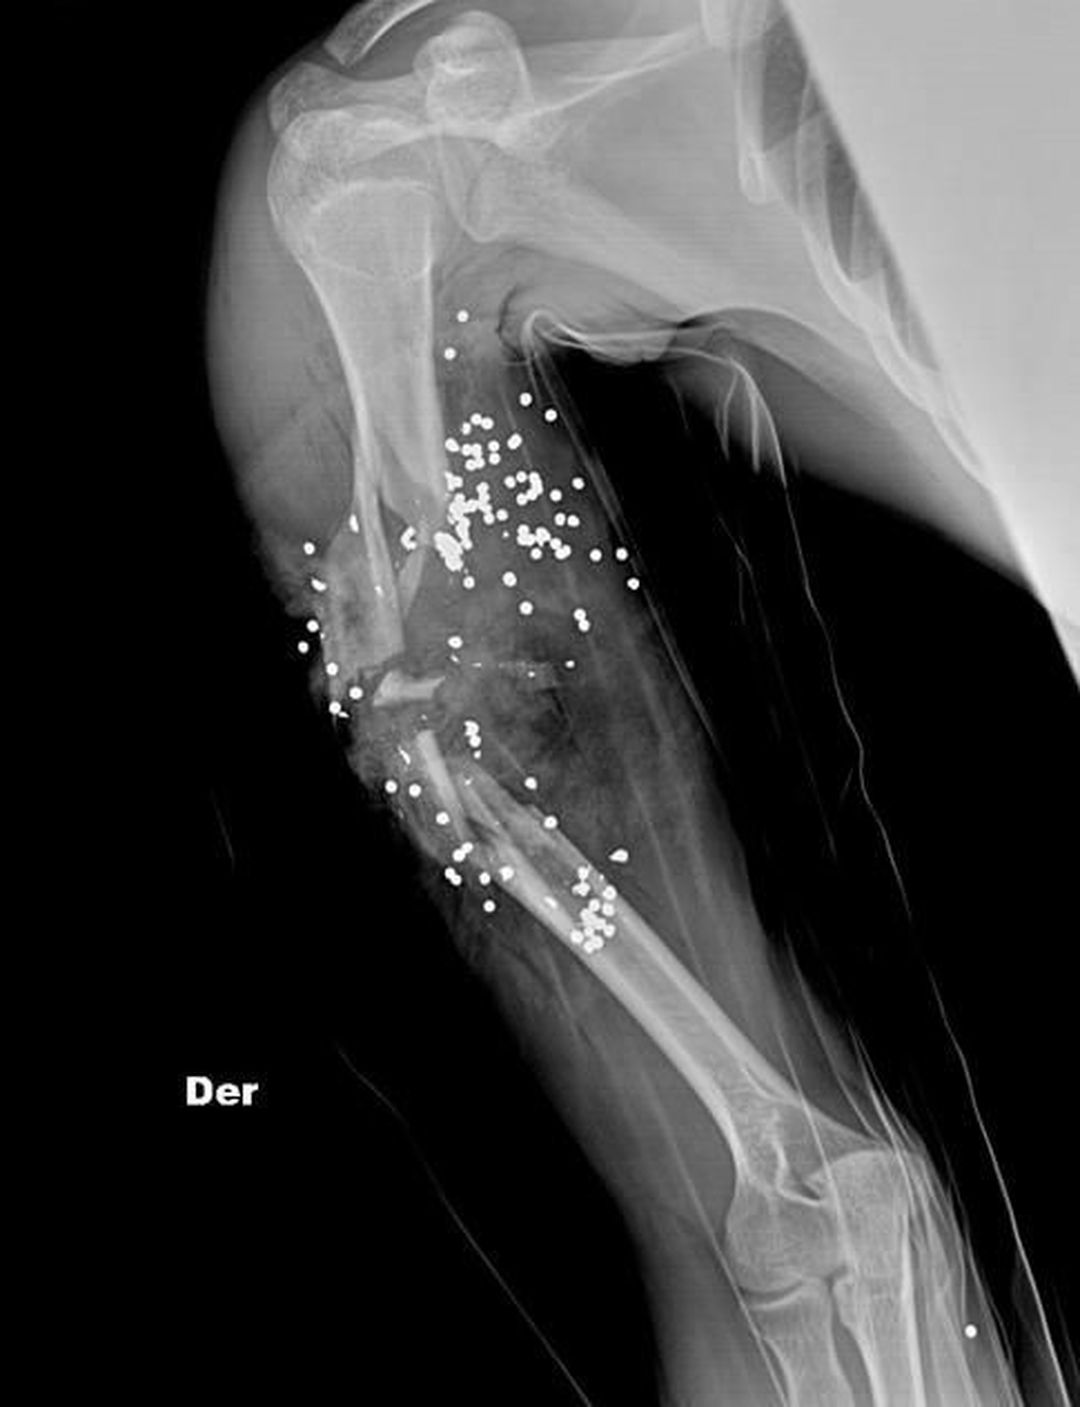

Gun shot wound in humerus

Radiology

Xray

Gunshot